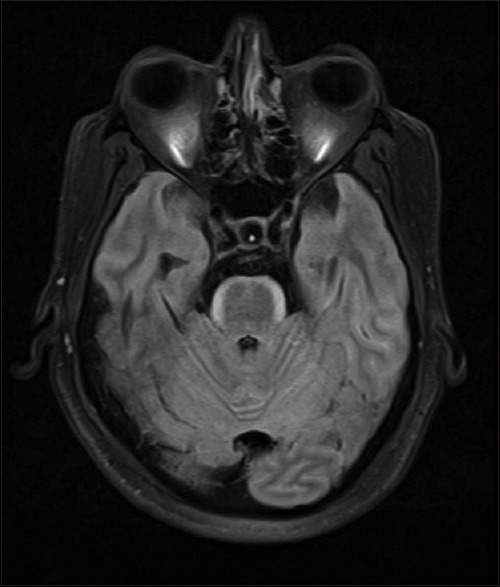

"Bloomy Rind on Cheese Sign" - A Radiological Biomarker of Leptomeningeal Metastasis.